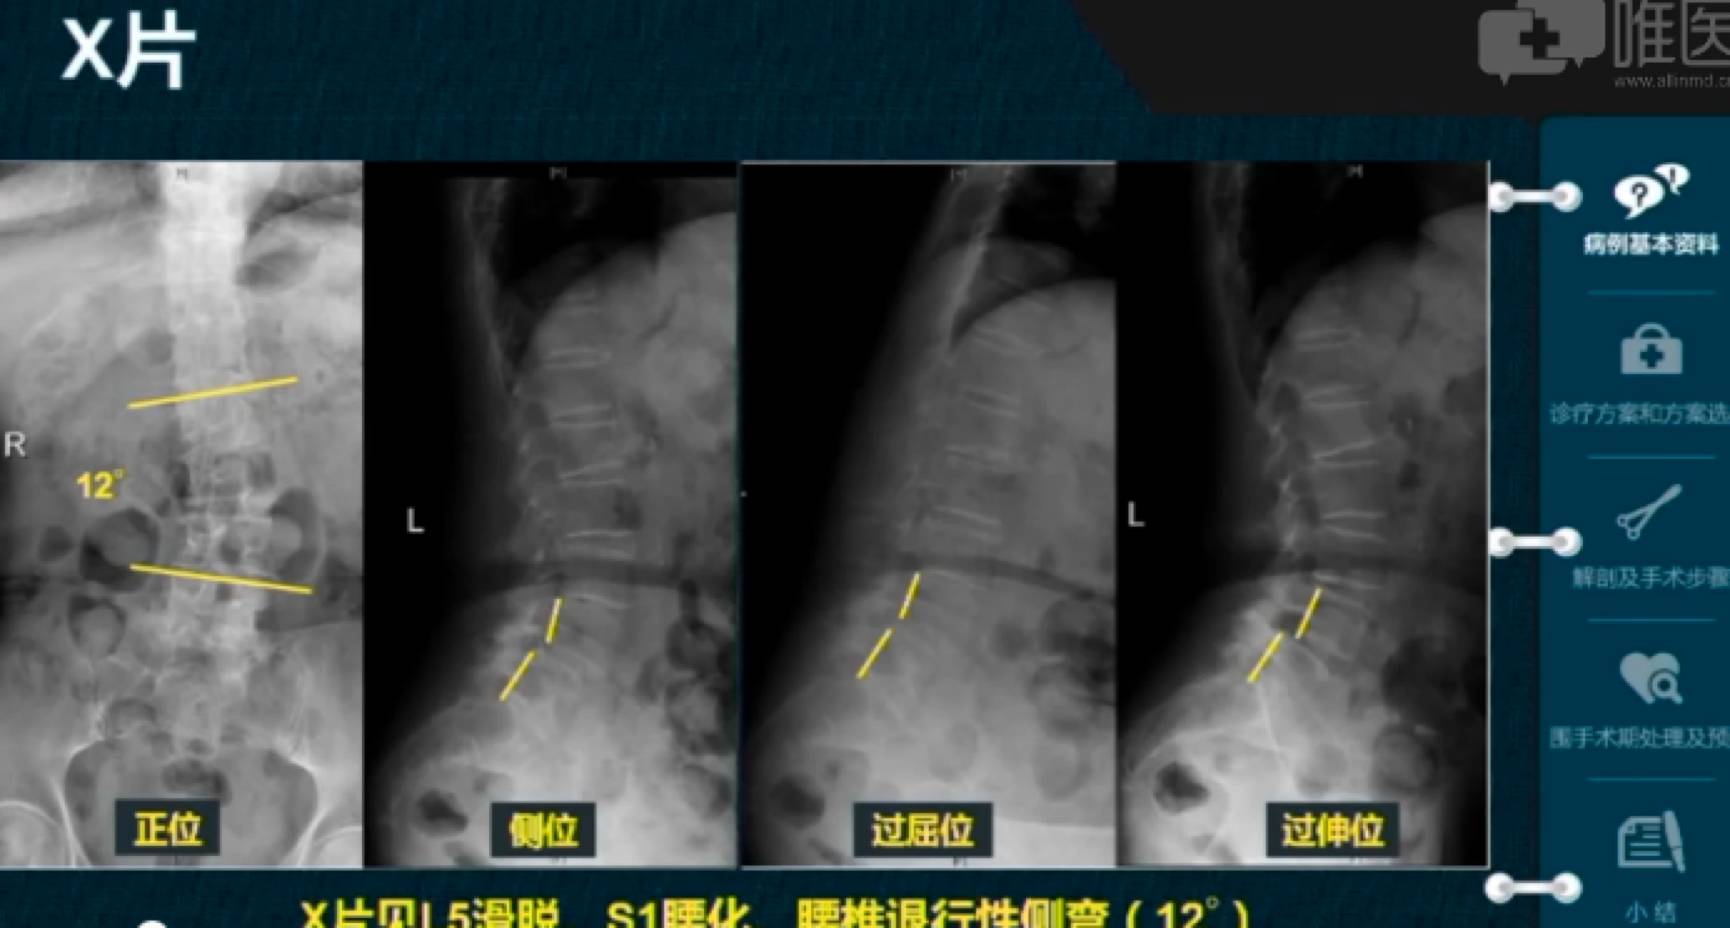

◈ 诊 断:L5滑脱(Ⅱ度)伴L5S1椎管狭窄、退行性腰椎侧弯、骨质疏松症、L2陈旧性骨松性骨折

▼ 术前影像